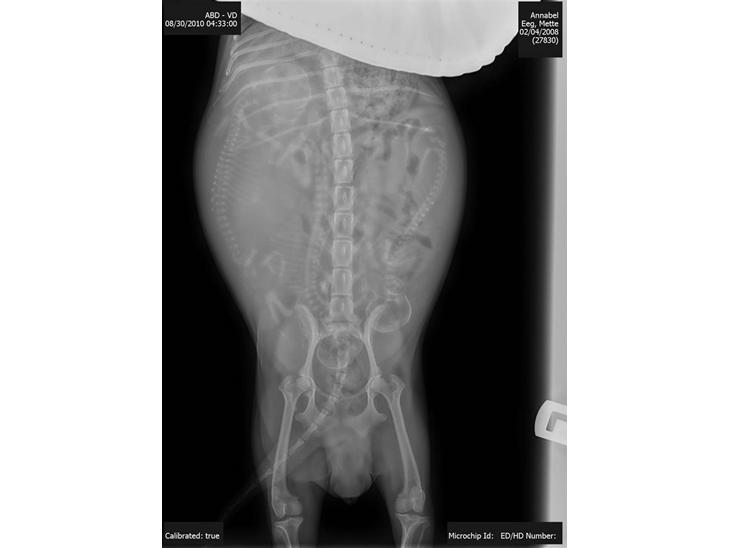

Her er rtg og billeder af bellas hvalpe...c kuldet